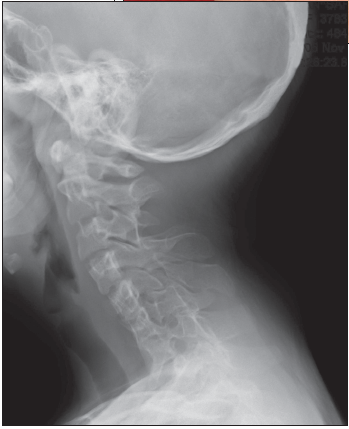

Radiograph of cervical spine as shown.

Lateral flexion-extension radiographs of the cervical spine confirm the diagnosis and establish the range of motion of each open interspace.2 A lateral radiograph of the skull will demonstrate occipitocervical abnormalities.10 MRI of the cervical cord and craniocervical junction is indicated before any orthopedic procedure and whenever neurologic symptoms or signs are present in the upper extremities.17